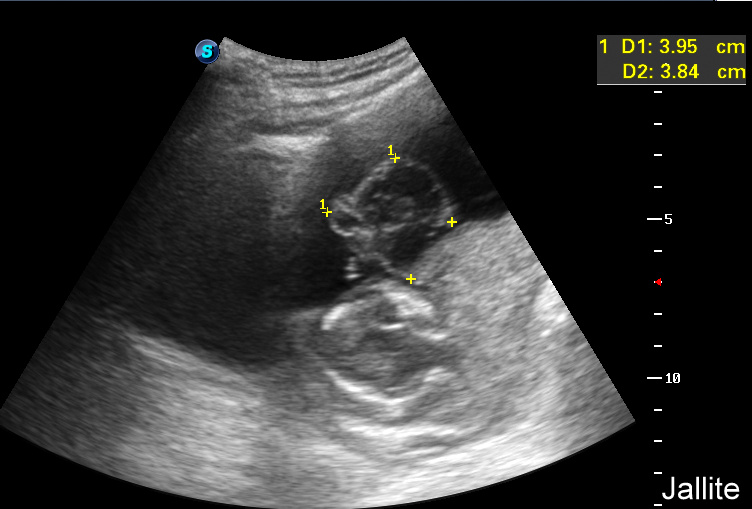

Ecografia 2D 11 semanas Higroma quistico pliegue nucal patologico Dr. Rafael Ortega Muñoz

HIGROMA QUISTICO MEDICINA FETAL PERÚ YouTube

Higroma quístico del primer trimestre Diagnóstico de hernia diafragmática congénita